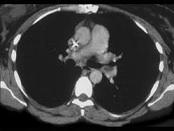

- 单项选择题女,51岁, 心脏手术后,突感胸痛, 结合CT图像,最可能的诊断是 ( )

A、肺栓塞

B、支气管扩张

C、肺水肿

D、肺癌

E、肺不张